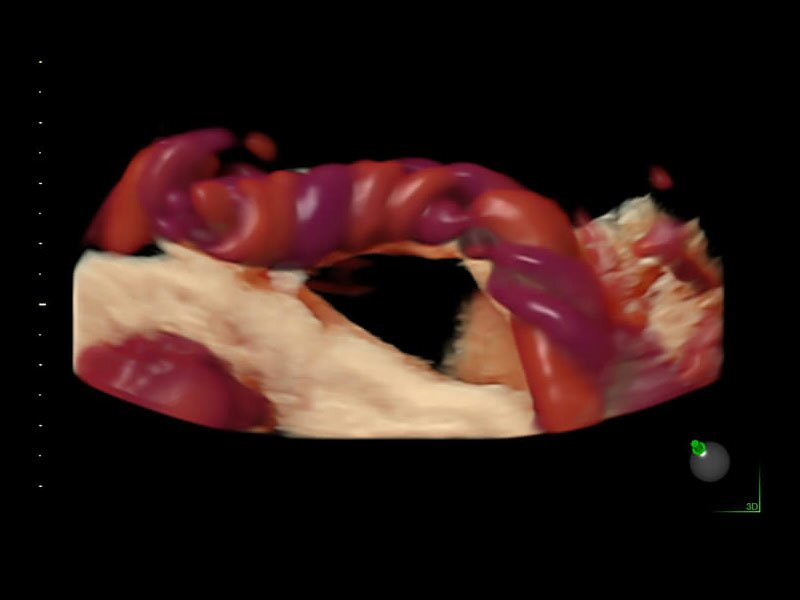

• Высокочувствительный допплер (HD-Flow)

• Реалистичный объёмный кровоток в режиме ЦДК (Radiantflow)

• HDlive Flow - перемещаемый источник света, совместимый с визуализацией кровотока в 3D

• Технология HDlive Flow — повышает реалистичность визуализации сосудистых структур, улучшая восприятие глубины (по сравнению с традиционным цветовым допплером и функцией HD-Flow).